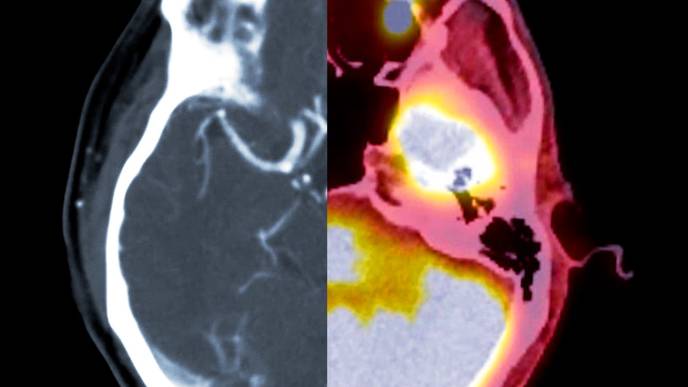

Participants who were eligible based on blood tests also underwent positron emission tomography (PET) scans, brain scans that are used to directly measure amyloid buildup in the brain. Among “plasma eligible” participants (those who met the blood test cutoff), individuals from all racial and ethnic groups were equally likely to be eligible to participate based on PET scan data. The study was just published in Alzheimer’s & Dementia: The Journal of the Alzheimer’s Association.